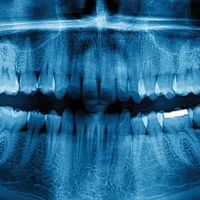

The human body is a remarkable creation; hidden within it lies the hardest material known to us, tooth enamel. This extraordinary armor protects our teeth, enabling them to endure the daily rigors of biting and chewing while contributing to a dazzling and confident smile. However, in some unfortunate cases, our teeth may succumb to the overwhelming pressures we impose upon them, leading to the distressing phenomenon of teeth breaking.

When our teeth begin to fracture, the concern is compounded by their relentless tendency to keep breaking, one after another. It’s common to think, “Why are my teeth breaking?” Fear not, we are going to explore the common causes of tooth breakage and discover preventive measures to safeguard your oral health.